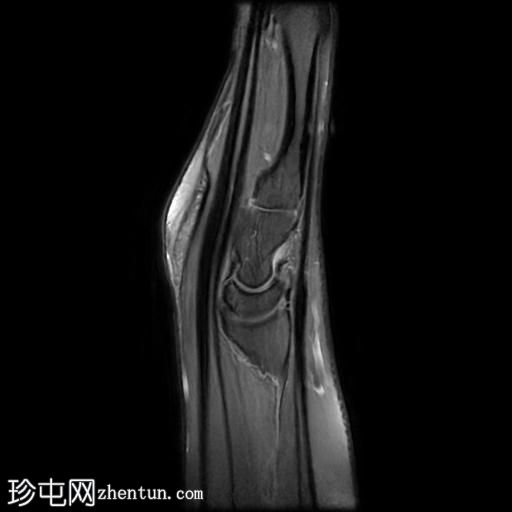

桡侧腕屈肌管综合征

持续性腕掌桡侧疼痛超过5个月。

MRI

矢状位

PD序列

脂肪抑制序列

桡侧腕屈肌腱鞘内可见液体信号,提示腱鞘炎

手部桡侧腕屈肌腱远端扁平,邻近的大多角骨嵴和舟骨结节可见反应性骨髓水肿

MRI结果提示存在桡侧腕屈肌腱病变,以及大多角骨和舟骨结节骨髓水肿。桡侧腕屈肌(FCR)肌腱病通常表现为腕关节掌侧(靠近桡侧)疼痛。这种情况通常是由于长期过度使用造成的,尤其是在肌腱与粗糙表面接触的部位。